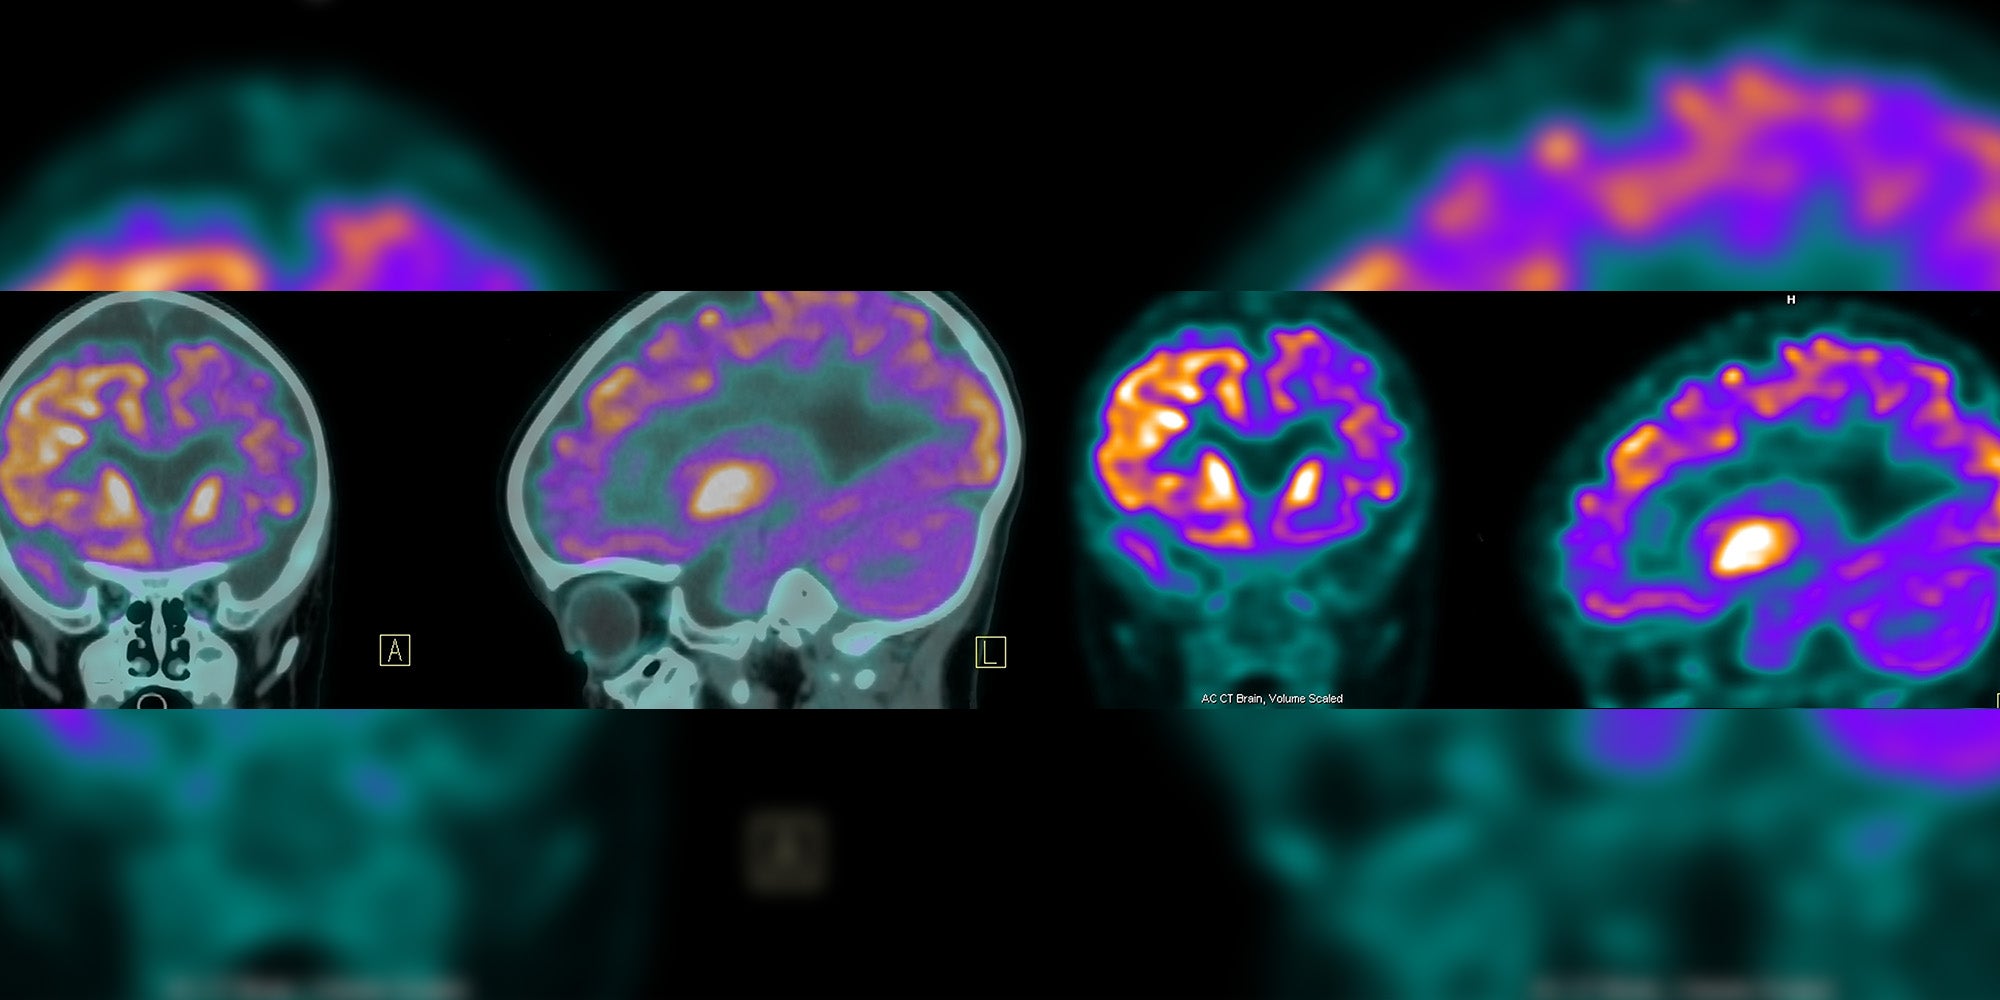

• Ischemic stroke, which is caused by narrowed or clogged blood vessels in the brain that cut off the blood flow to brain cells. More than 80 percent of strokes are ischemic.

• Hemorrhagic stroke, also called a brain hemorrhage or “brain bleed,” which occurs when a blood vessel ruptures in or near the brain.